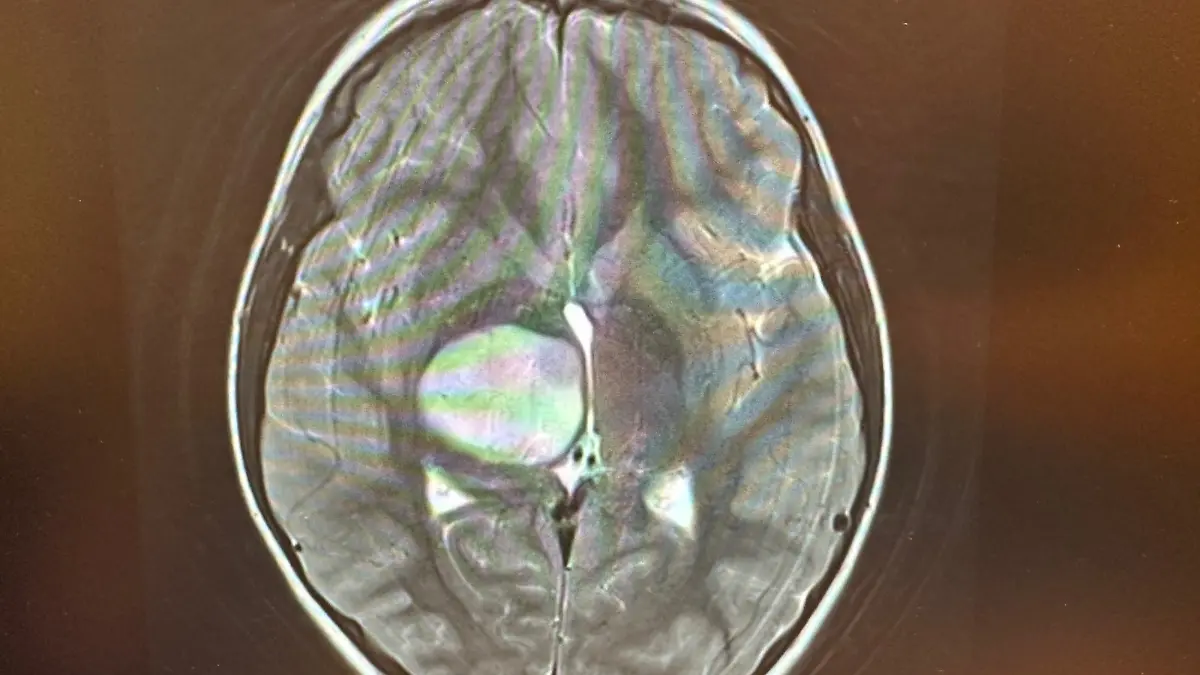

Dann geht es für Isi und ihre Eltern zum Hausarzt. Von dort geht es weiter ins MRT. Es ist der siebte März 2024, der Moment, in dem das Leben der Familie aus den Fugen gerät. Schon auf den ersten Bildern ist der Tumor sichtbar. Ihre erste OP bekommt sie am 27. März. Was bleibt, ist eine fünf Zentimeter lange Narbe am Hinterkopf und noch schlimmer: der Tumor. Ein paar Wochen später wird klar, dass dieser bösartig ist. „Dann ist für uns die Welt zusammengebrochen“, sagt Timo Kampe zu RTL.

Die genaue und grausame Diagnose: Diffuses Mittelliniengliom. Dieser Tumor sitzt tief im Kopf und drückt auf die Motorik. Das erklärt Isis Lähmungserscheinungen. Wenn sie isst und ihr läuft etwas auf der linken Seite runter, dann merkt sie es nicht. Den linken Arm und das linke Bein kann sie nicht steuern, sobald sie den linken Arm hebt, zittert sie enorm. Ihre Pupillen arbeiten nicht gleichmäßig schnell. Wirksame Chemotherapien gibt es nicht, eine operative Entfernung ist nicht möglich. Die einzige Therapie ist Bestrahlung – die aber bei Isi auch nicht langfristig geholfen hat. Familienvater Timo Kampe zu RTL: „Wenn ein Arzt dir in der Klinik sagt, dass die Tochter das schlimmste im Kopf hat, das irgendwie möglich ist. Da bin ich zusammengebrochen.”